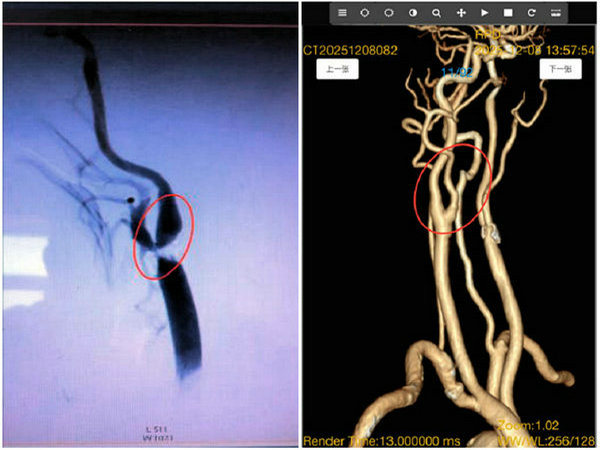

术前影像(血管狭窄) 术后影像(血管畅通)

手术过程中,麻醉科主任孙宝文教授精准麻醉管理,电生理科主任韩国超实时监测保驾护航,王洪军教授凭借精湛的手术技艺与丰富的临床经验,协同刘增良教授、刘洋教授团队沉着操作,在高清视野下精准剥离堵塞血管的病变斑块,彻底清除血管通路障碍。整个手术流程规范、动作精准,有效规避了血管损伤、微栓子脱落等术中风险。术后影像学检查显示,王先生狭窄的颈内动脉血管恢复通畅,血流动力学指标完全正常,目前恢复良好,已顺利脱离脑血管疾病高危状态。